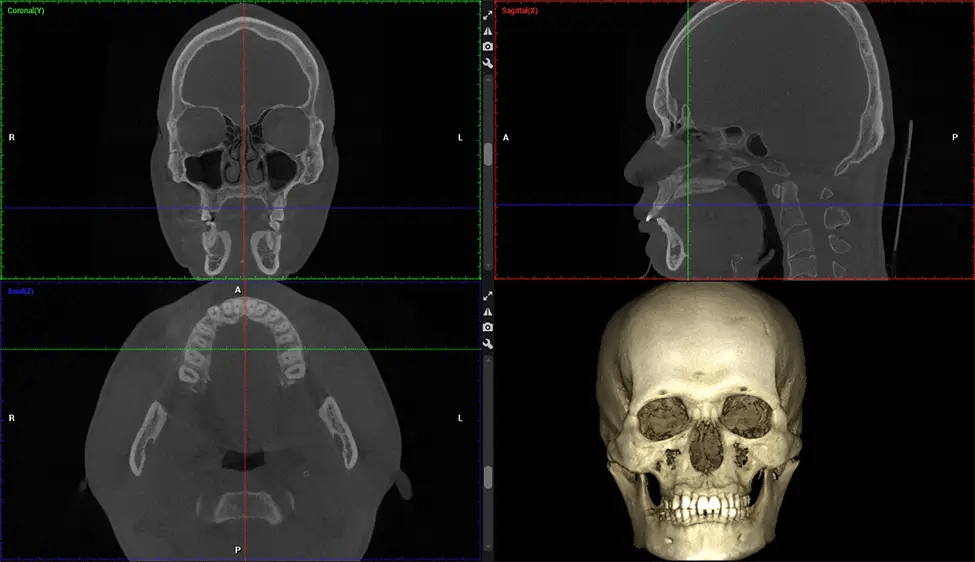

Cráneo completo hasta C7 de la columna vertebral

Tomografía computarizada de haz cónico (CBCT) es una técnica de imagen avanzada utilizada en odontología y cirugía maxilofacial para obtener imágenes 3D detalladas de las estructuras orales y maxilofaciales. Dr. G Estudio Dental, nuestro CBCT Los escáneres utilizan un haz de rayos X en forma de cono y un detector especializado para capturar imágenes desde diferentes ángulos. Posteriormente, una computadora combina estas imágenes para crear una representación tridimensional de la anatomía oral del paciente.

Planmeca Viso G7 CBCT La tomografía computarizada de haz cónico (CBCT) está diseñada para superar las exigencias de los líderes de la industria, los especialistas y las grandes instituciones. Cuenta con un sensor de gran tamaño (25 × 30 cm) con cuatro cámaras integradas. Puede capturar tamaños de volumen ilimitados, desde ø3×3 cm hasta ø30x30cm, capturando el casquete escutelario a través de C7 en la columna cervical. Planmeca Viso G7 ofrece el escaneo de volumen único más grande de la industria de ø30×19 cm. Está preparado para manejar modalidades de imágenes avanzadas como la tecnología Planmeca ProFace® y Planmeca 4D™ Jaw Motion. El soporte occipital para la cabeza permite una visión sin obstáculos del tejido facial.